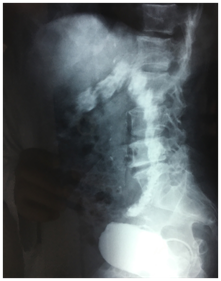

An antibiotherapy was started and retrograde and urinary uretro-cystography was performed. Retrograde cystography showed diverticular bladder with opacification of the sigmoid colon up to the half of the transverse colon (Figure 1) (Figure 2).

Figure 1 Frontal view of retrograde urethrocystography showing opacification of the sigmoid and descending colon.

Usually, Because of high pressure in the intestine, the fistula works from the intestine to the bladder except when there is an obstacle on the lower urinary tract, as was the case of our patient resulting in opacification of the intestine during cystography thus permitting diagnosis of entro-vesical fistula.